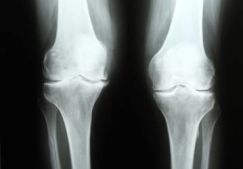

Рентген суставов

Рентген-диагностика суставов является одним из ведущих методов исследования нарушений костно-суставного аппарата. Именно на рентгеновских снимках можно увидеть признаки патологии: нарушения соответствия суставных поверхностей, костные разрастания по краю хряща, участки отложения...